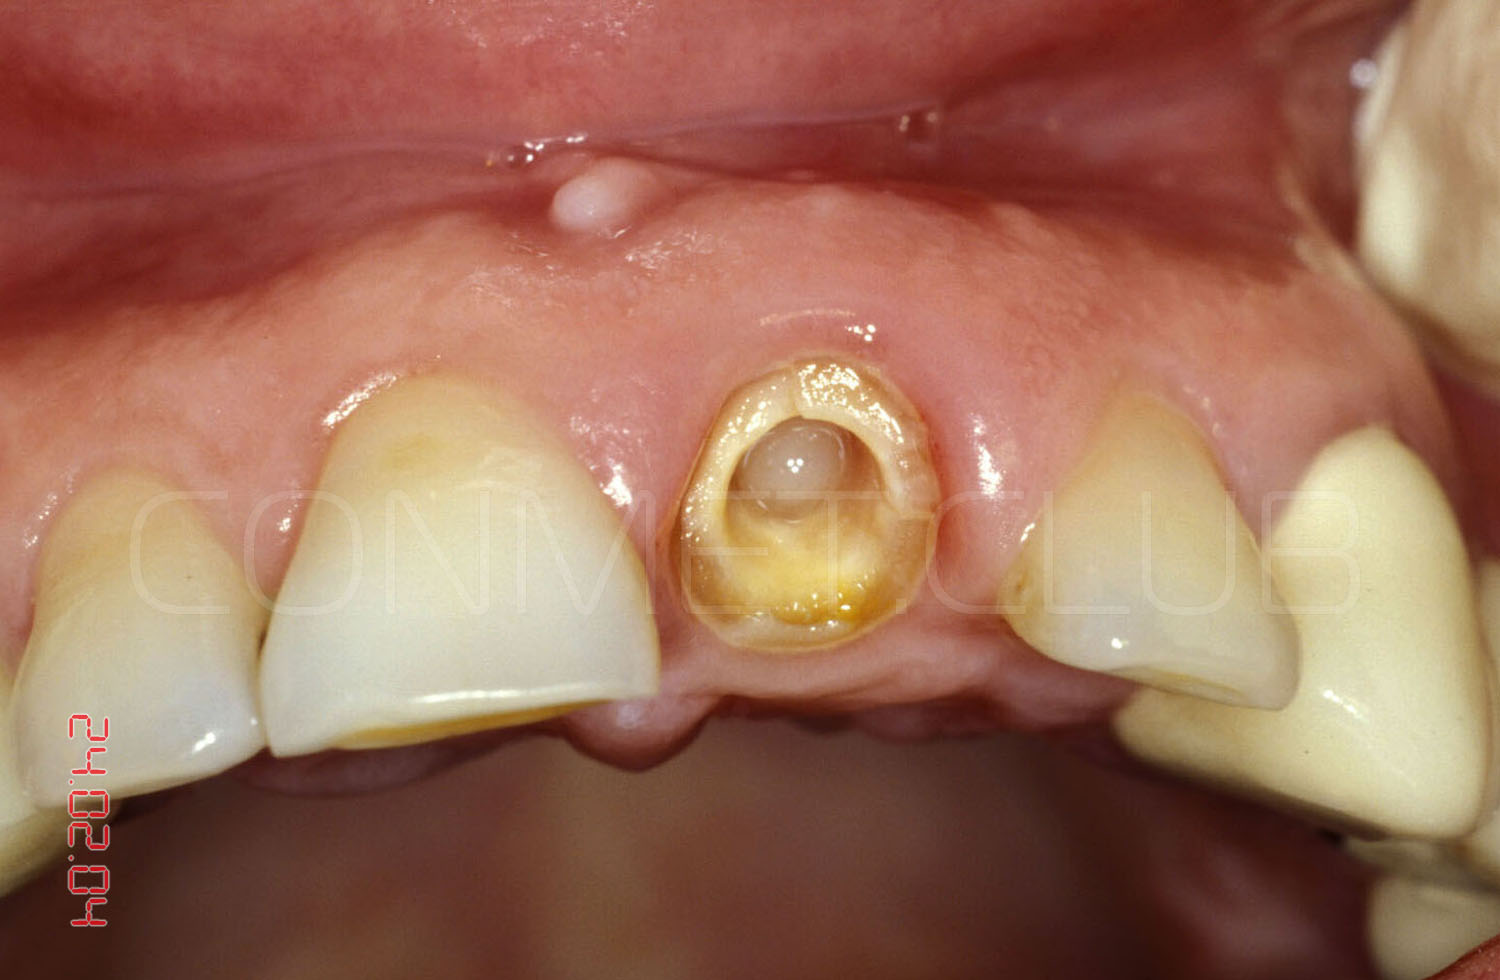

Операция немедленной имплантации была произведена 27.02.2004 года непосредственно после экстракции зуба 21 из-за невозможности дальнейшего лечения данного зуба (две вертикальные трещины корня).

Вид на корень и трещины за три дня до экстракции и немедленной имплантации.

Вид на лунку удаленного зуба. Щипцы при удалении не использовались, только кюретажная ложка СМ 2/4 и прямой элеватор.